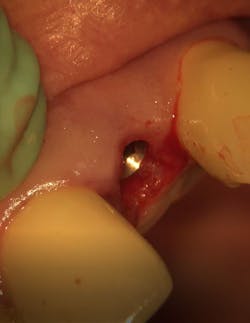

The decision to use the Ditron Implant System was based on the following treatment plan: extraction and immediate implant placement, with immediate provisionalization using a final titanium abutment. Extraction and immediate implant placement with immediate provisionalization have shown to be quite successful.

Maintaining initial stability is important when an implant is placed in a compromised extraction site, since there is less bone-to-implant contact there than in a healed site. Because of its architecture, the Ditron Ultimate implant offers a very high initial stability and strong abutment connection. The implant profile uniformly distributes the stress directly to the bone, which results in a more even distribution of force and lower long-term crestal resorption. This implant system has a good aggressive thread profile and a secure abutment connection, which are both key characteristics. The microthreads on the implant’s reverse conical neck (RCN) greatly increase the implant’s ability to resist axial displacement, and the mechanical stimulus the microthreads provide helps to preserve the peri-implant marginal bone. By inserting an Ultimate implant, 5.57 mm3 of bone will be saved compared to that of a non-RCN implant.7

First visit: Extraction and immediate implant placement, immediate placement of the final abutment prepared intraorally, and then a provisional out of function.